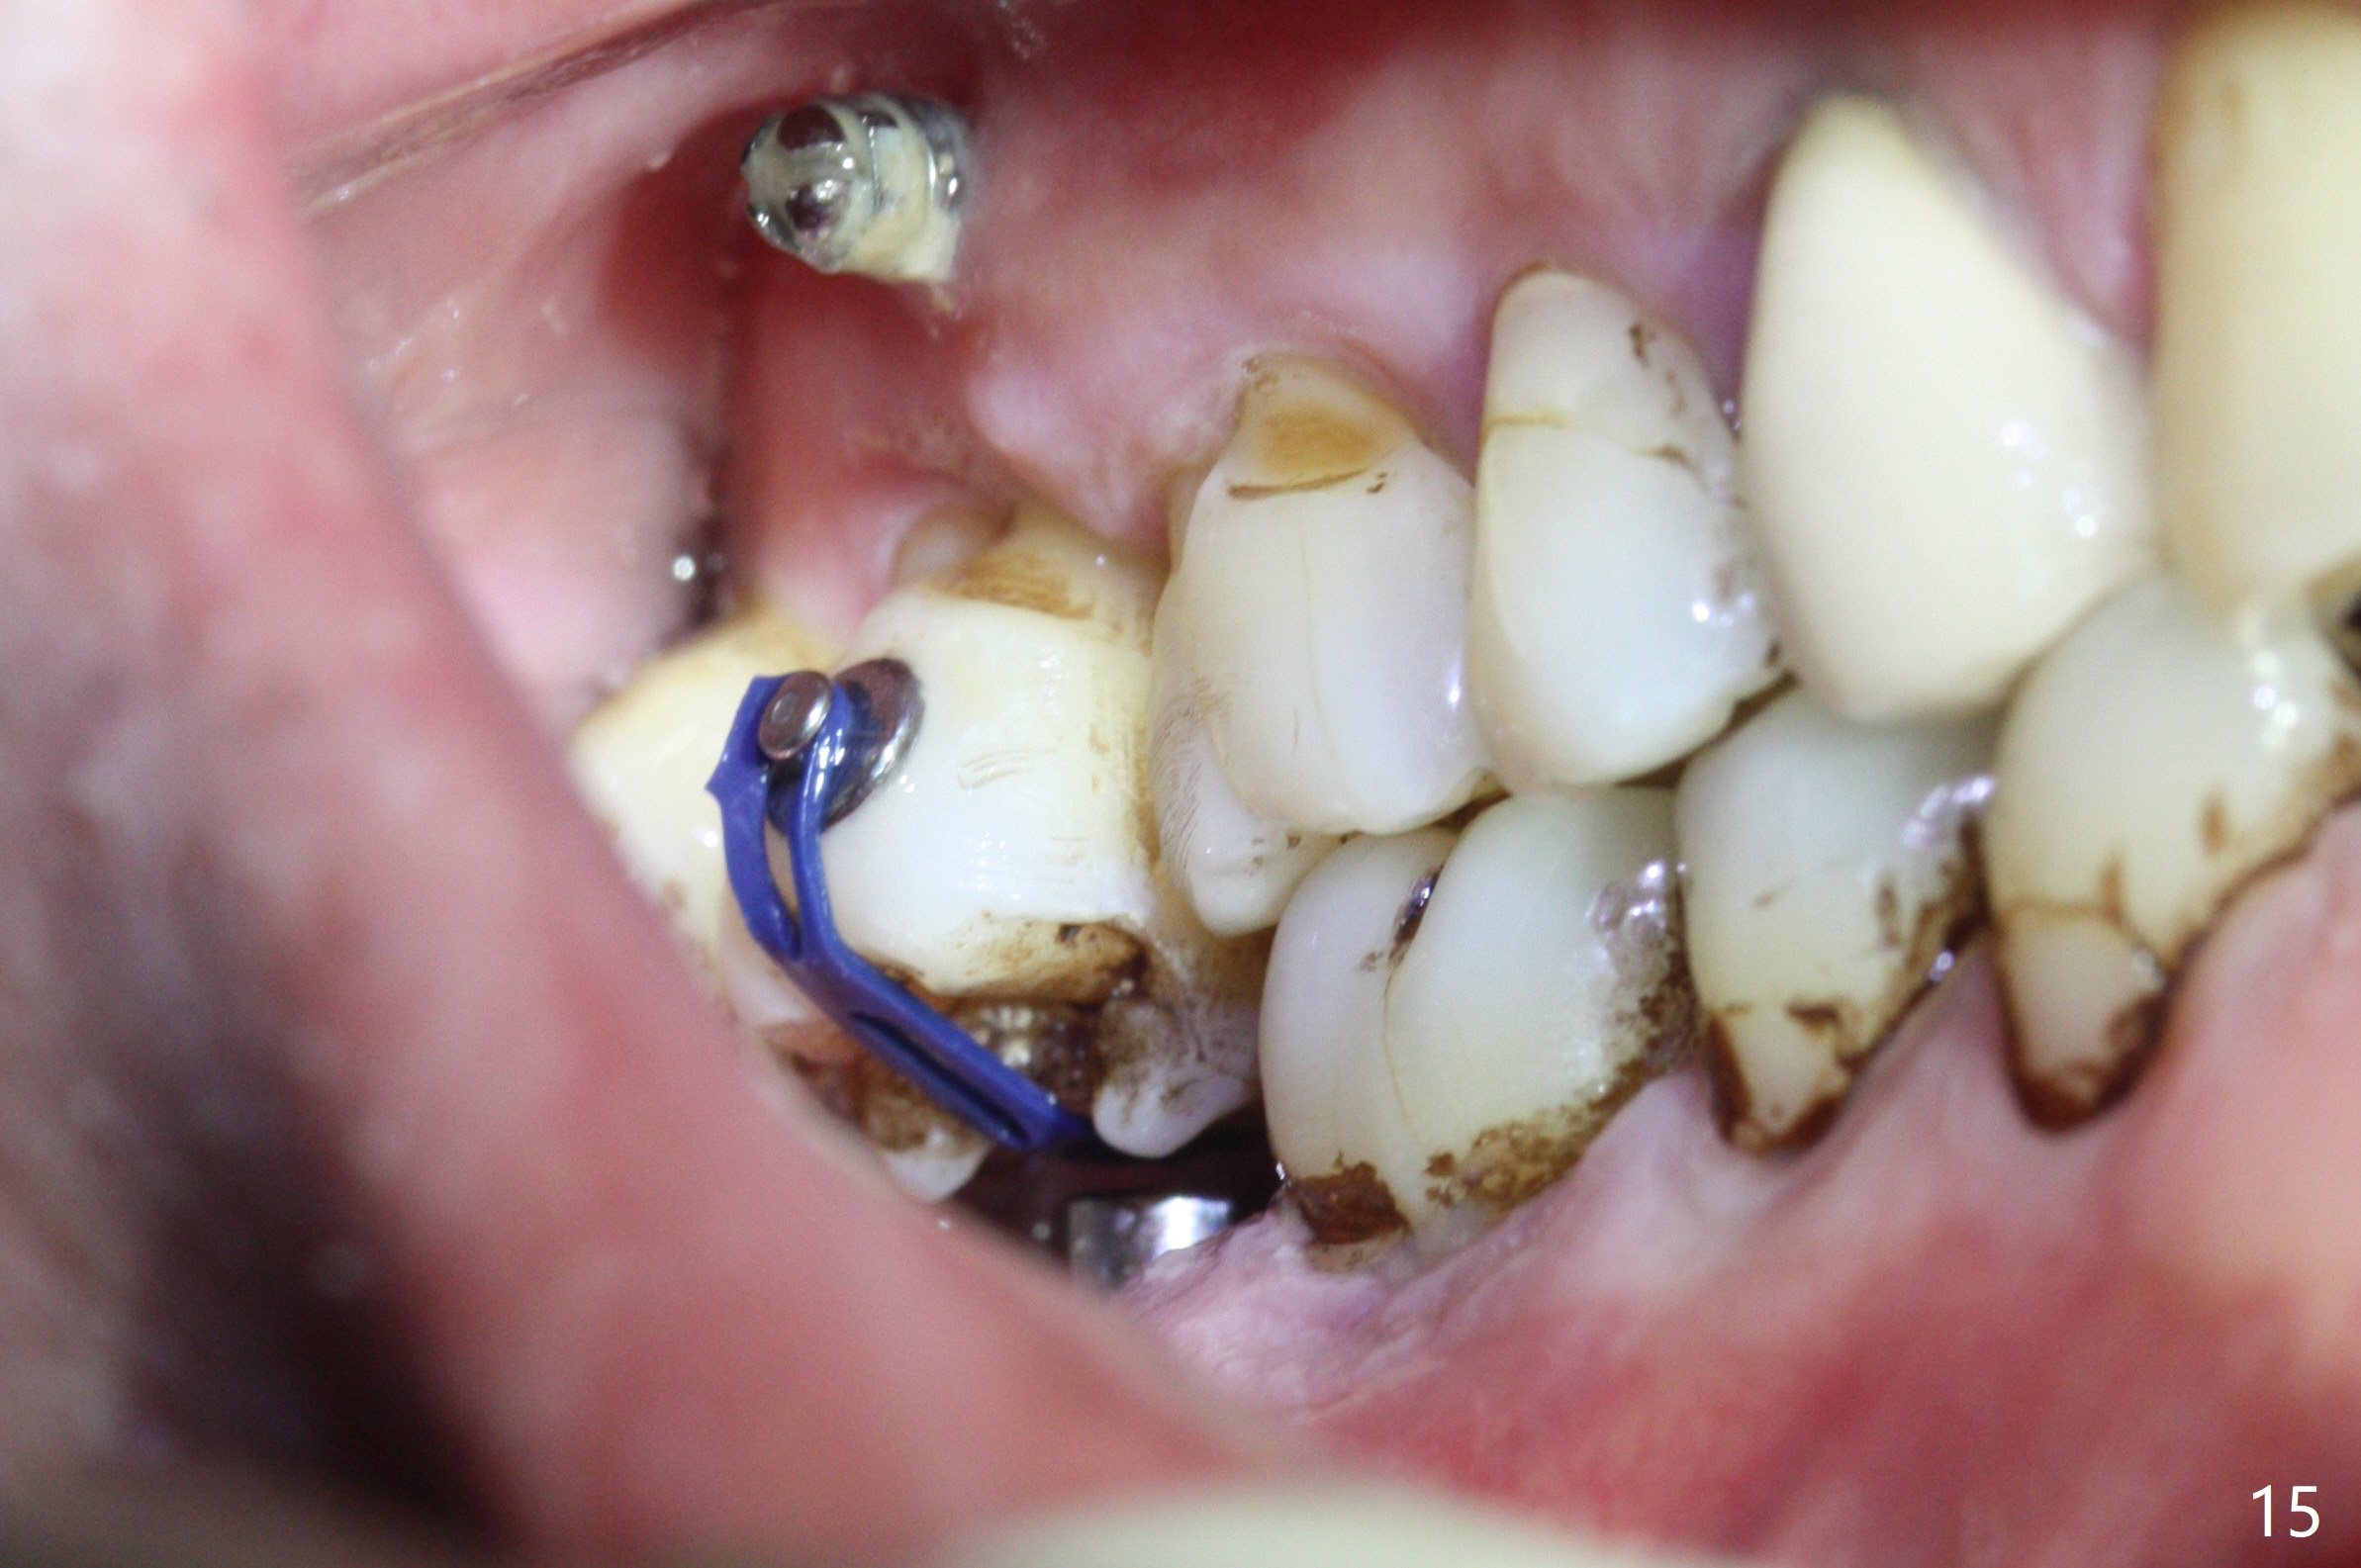

Two days post #31 implant placement, the patient returns for orthodontic intrusion of the tooth #2 with mini-implants (Fig.1). The palatal cusps have been trimmed (Fig.2 ^), since they almost contact a healing abutment at #31(*, Fig.3). Two mini-implants are to be placed mesiobuccal and distopalatal to the affected tooth. After minimal injection of Lidocaine, a 1.6x6 mm Tomas implant is placed in full length mesially (Fig.4), while the other (1.6x8 mm) half way (Fig.4). Following change in implant site mesially (Fig.6 >), the implant is half inserted (Fig.5). It appears that the tip of the distal implant is toward the tooth #1 (Fig.5). After withdrawing the implant partially, it is re-directed to apparently ideal trajectory (Fig.7). Ideally the mesial implant (Fig.8) should have been placed partially initially (Fig.4,5,7) so that the trajectory could have been able to be changed.

The buccal implant becomes loose in 2-3 months. When the wound heals (Fig.9 <), a 1.6x`10 mm implant is placed with the help of PAs for trajectory (Fig.10,11) and in the nonkeratinized gingiva (higher, the crestal bone may have been traumatized by previous implant placement, Fig.12). Two months later, the tooth #2 is partially intruded (Fig.13). A provisional (Fig.14 P) is fabricated in the osteointegrated implant at #31 with supraocclusion so that the remaining dentition has no occlusal contact (*). The periodontally compromised tooth #2 becomes in buccoversion in 2 months. The provisional is removed, while a lingual button is placed in the buccal surface of the tooth #2 (Fig.15). With power chain attached to the lingual mini-implant, the tooth #2 is lingualized in 2 months. The provisional and the implants are reused for final intrusion (Fig.16). The treatment is nearly 11 months. The buccal implant, although placed in the movable mucosa, remains stable and healthy (Fig.17). The tooth #1, as a guiding plane (to prevent #2 from distalization during intrusion), is not extracted after intrusion is completed.